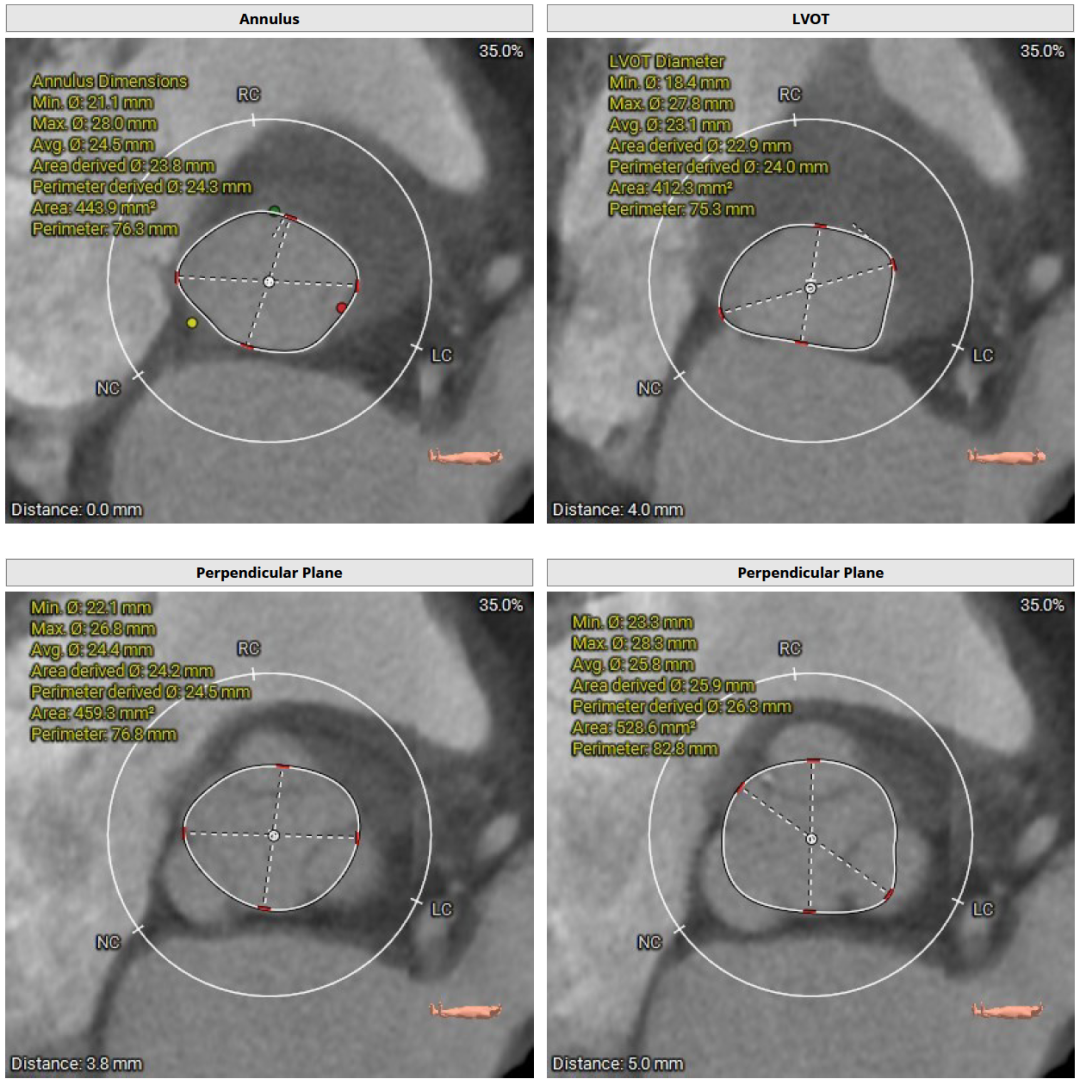

CT评估及手术策略

患者为三叶式主动脉瓣,重度反流。瓣叶交界轻度钙化。瓣环周长76.3 mm,平均径24.3 mm。LVOT周长77.3 mm,平均径24.0 mm。瓣上3.8 mm、5.0 mm、8.9 mm处空间为76.8 mm、82.8 mm、78.3 mm。STJ 周长105.7 mm,高度23 mm,升主周长126.5 mm 增宽、瓦氏窦大。综上所述建议TAV 27 瓣膜。左右冠高度15.6 mm、17.2 mm相对瓣膜支架可,冠脉风险低。股动脉入路血管轻度迂曲,双侧股动脉分叉高度可。腹主动脉、双侧髂总动脉散在钙化斑块。右侧股动脉平均内径最小6.3mm,左侧股动脉平均内径最小5.8mm,建议选择右侧股动脉为主入路。